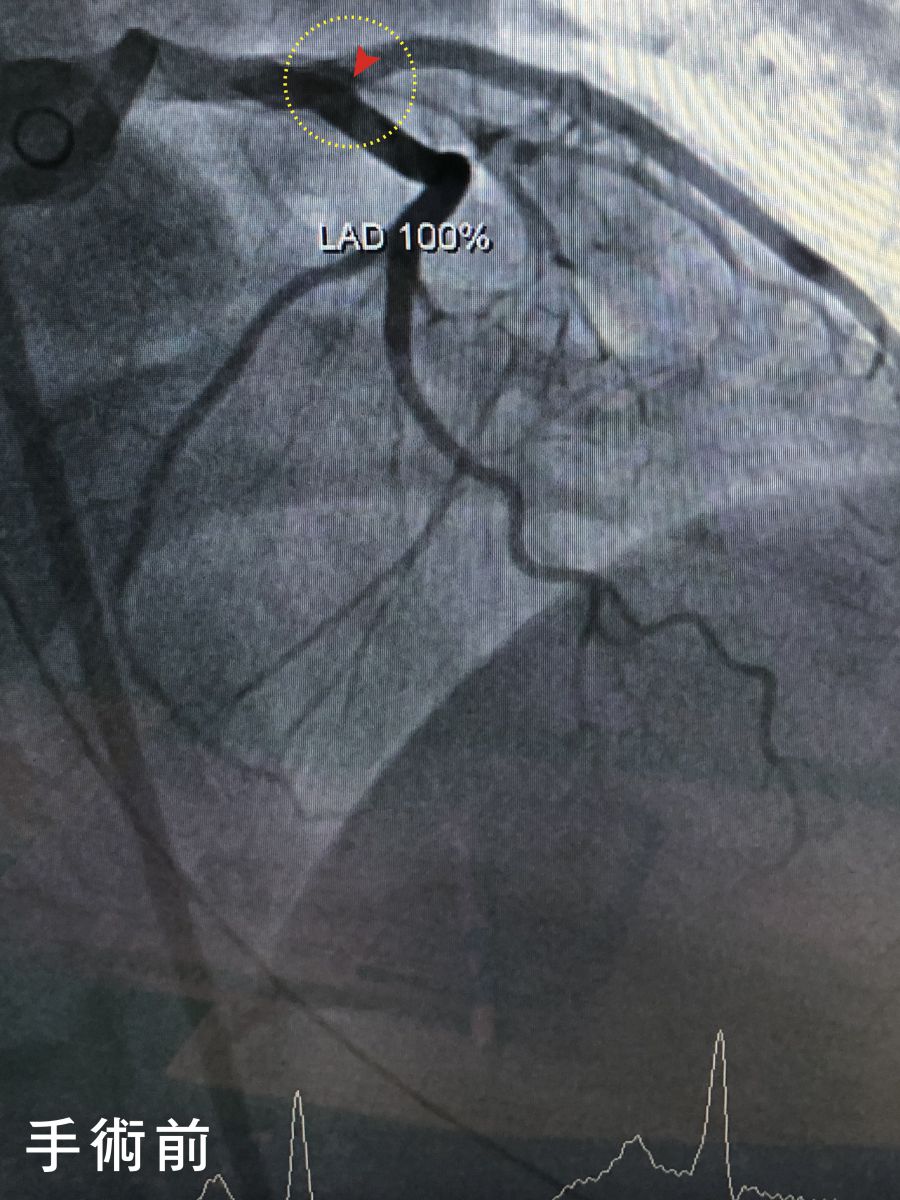

圖:紅圈處即為梗塞位置手術前後差異

光田綜合醫院重症醫學暨心臟內科醫師柯君樺表示,病人到院檢查發現心臟左前降枝冠狀動脈完全堵塞,右冠狀動脈血栓,經心臟內科黃世忠主任醫師率領之心導管團隊快速搶救在50分鐘內成功完成左前降枝冠狀動脈疏通手術、穩定心血管狀況,續進入低溫治療後逐漸清醒,再經2周治療檢查右冠狀動脈血栓也已消失,未來持續復健、服藥和回診追蹤即可。